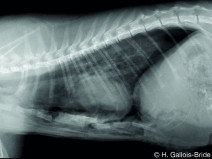

• Radiologie interventionnelle : se lancer et voir plus loin !

Le Groupe d'Étude en Chirurgie est heureux d’organiser sa 9è journée spécialisée sur le thème de la radiologie interventionnelle, le 29 janvier 2026. Cette journée annuelle de formation vise un public de vétérinaires ayant un fort intérêt pour la chirurgie des tissus et la chirurgie mini-invasive. Elle se tiendra au siège de l'AFVAC Paris 8è.

Cette année, nous avon...

Le 29 janvier 2026

Paris (75008)

Chirurgie

Oncologie

G.E.C.

2080